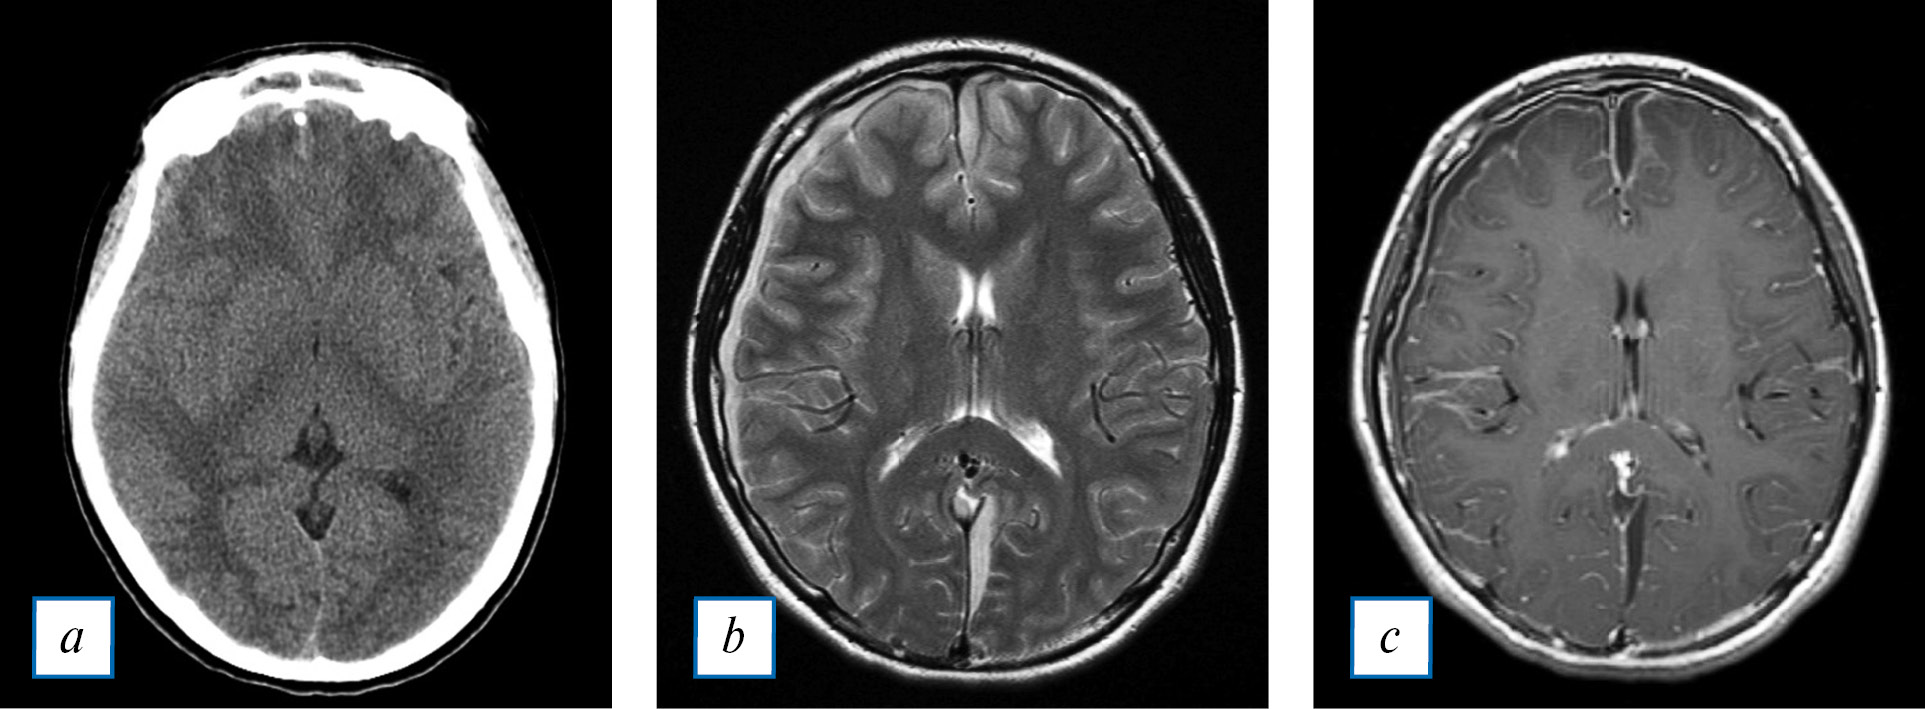

КТ головного мозга проводится в основном при осложненном течении серозного менингита и направлена на выявление тяжелых нарушений, таких как дислокационный и гидроцефалический синдромы [8, 9]. Расширение субарахноидального пространства регистрируется у 50% пациентов с БГМ [6]. В тоже время роль КТ в оценке прогноза течения серозного менингита в настоящее время не изучена [10, 11]. Проведенный нами анализ доступной литературы не дал работ с указанием конкретных значений чувствительности, специфичности и общей диагностической ценности данных методов. Все сведения носят разрозненный, иногда декларативный характер [9–11]. Отечность извилин и сглаженность борозд являются характерными и в тоже время неспецифичными признаками менингита, выявляемыми при проведении нативной КТ и МРТ [12, 13]. МР-визуализация является наиболее чувствительным способом выявления менингита: может быть видна аномальная гиперинтенсивность на FLAIR(fluid-attenuated inversion recovery — восстановление инверсии с ослаблением жидкости) и DWI-изображениях (b >800 с/мм2) вдоль мозговых борозд.

Приблизительно у 55–70% пациентов с клинически доказанным менингитом при внутривенном контрастировании возможно обнаружение тонкого линейного накопления контрастного вещества в бороздах коры головного мозга [5].На сегодняшний день показано, что чувствительность импульсных последовательностей FLAIR и DIR (double inversion recovery — восстановление двойной инверсии) в выявлении патологических изменений в оболочках головного мозга превосходит чувствительность T1-взвешенных изображений (Т1-ВИ) вследствие подавления МР-сигнала от нежелательных тканей и меньшей зависимости от неоднородности магнитных полей [14] (рис. 1).

Рис. 1. МРТ головного мозга пациента в возрасте 3 лет с бактериальным менингитом. Диффузное усиление МР-сигнала в FLAIR-режиме в области борозд мозга (a), изоинтенсивное — в режиме DWI (100 с/мм2) (b), без МР-признаков накопления контрастного вещества (c). Фокальные субкортикальные изменения без признаков повреждения гематоэнцефалического барьера (собственные данные).

Fig. 1. Brain MRI of a 3 year-old patient with bacterial meningitis. Diffuse increase in the MR signal in the FLAIR mode in the furrows of the brain, isointense in the DWI mode (1000 s/mm2), no signs of the contrast accumulation. Focal changes in the subcortical parts of the brain without signs of blood-brain barrier disturbance.